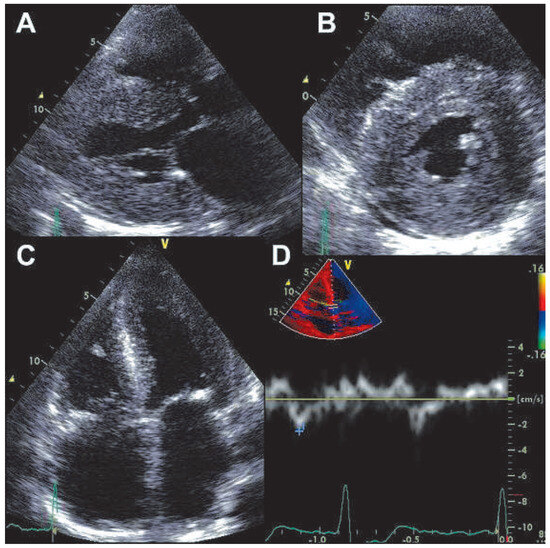

A 66-year-old woman was referred because of suspected acute coronary syndrome (ACS). On admission the patient was complaining of chest pain irradiating into her back, and she also had shortness of breath on minimal exertion and even at rest. Blood pressure was 134/89 mm Hg, pulse was regular (82 bpm). Physical examination revealed evidence of biventricular cardiac decompensation with lower leg edema, congested neck veins, and bibasilar crackles. Chest X-ray confirmed pulmonary venous hypertension. The ECG showed sinus rhythm and extensive pathological Q waves in leads II, III, and aVF as well as the praecordial leads V1–V4 (Figure 1). Plasma concentration of B-type natriuretic peptide was 3287 ng/l (normal <50 ng/l), and cardiac troponin I was mildly elevated (1.92 µg/l, normal <0.5 µg/l). There was evidence of renal failure (estimated glomerular filtration rate 35 ml/min/1.73 m2). The bedside echocardiogram (Figure 2) performed for triage of ACS revealed a normal-sized left ventricle with symmetrically and massively increased wall thickness (left ventricular end-diastolic diameter 43 mm, interventricular septum 28 mm, posterior wall 23 mm) with a speckled appearance of the myocardium, diffusely impaired contractility (left ventricular ejection fraction 35–40%, long axis shortening virtually absent, radial shortening preserved), a restrictive mitral inflow pattern with significantly reduced tissue velocities (peak early diastolic mitral annular velocity [e’] measured at the septal annulus 3 cm/s), biatrial dilatation, and a small pericardial effusion. Ultimately a diagnosis of AL-amyloidosis was obtained based on amyloid deposits in the abdominal fat pad fine needle aspirate and free light chains in serum. Bone marrow biopsy did not show evidence of multiple myeloma. Chemotherapy with alkeran, dexamethason, and thalidomide was initiated but the patient died six weeks after the initial presentation.

Figure 2. Transthoracic echocardiogram. Panel A: parasternal long-axis view showing symmetrically increased left ventricular wall thickness and left atrial dilation. Panel B: parasternal short axis view showing symmetrically increased left ventricular wall thickness with concentric left ventricular geometry and small pericardial effusion. Panel C: apical four chamber view showing symmetrically increased left ventricular wall thickness and biatrial dilatation. Panel D: pulsed wave tissue Doppler recording at the septal mitral annulus showing significantly reduced peak early mitral annular velocity.

The ECG in this patient showed pathological Q waves suggestive of previous inferior and anterior myocardial infarction. However, everything in the echocardiogram did not fit such a diagnosis but showed many very typical features of cardiac amyloidosis. A so-called “pseudoinfarction pattern”, i.e., the presence of pathological Q waves, typically in leads II, III, and aVF and V1–V4 without echocardiographic evidence of a previous myocardial infarction is a typical ECG feature in cardiac amyloidosis, which can be found in more than 50% of these patients (83% [1] and 60% [2] respectively in two large series). Although a pseudoinfarction pattern is not specific for cardiac amyloidosis [2], a pseudoinfarction pattern combined with a very typical echocardiogram allowed us to reach the diagnosis in the present case. Notably, chest pain is not rare in patients with cardiac amyloidosis [3]. It has been suggested that diffuse narrowing of the small coronary vessels due to amyloid deposition may result in the development of clinically significant myocardial ischaemia [3]. However, elevated cardiac troponin does not necessary indicate ACS in patients with amyloidosis but is a marker of a poor prognosis [4], possibly as an unspecific marker of ischaemic or non-ischaemic (amyloid infiltration) myocyte damage. In the present patient, coronary angiography was not performed due to the high risk of worsening of renal failure.